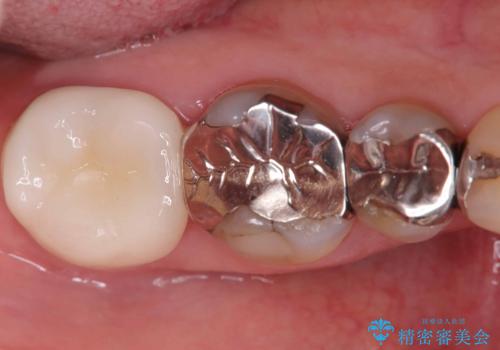

銀歯の下の虫歯|オールセラミッククラウン

担当医 河野豊嘉

奥歯に虫歯があると言われた セラミッククラウンでキレイで長持ちする歯へ

担当医 榊原康平